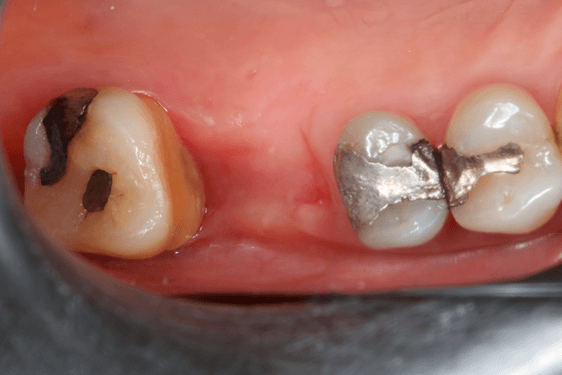

A preservação do alvéolo é uma opção de tratamento, evitando ou reduzindo a perda óssea. Alguns procedimentos são sugeridos com o objetivo de reduzir essa perda fisiológica, como a utilização de biomateriais preenchendo o alvéolo, barreiras, instalação de implante imediato entre outros. 4

Avaliamos o desempenho do biomaterial de hidroxiapatita com colágeno tipo I (Extra Graft XG-13®) na manutenção do volume alveolar.

A aplicação como o caso clínico abaixo se mostrou uma técnica acessível a todos cirurgiões dentistas, pois se trata de um procedimento de simples execução e acessível. Logo, deveria constar na clínica diária.